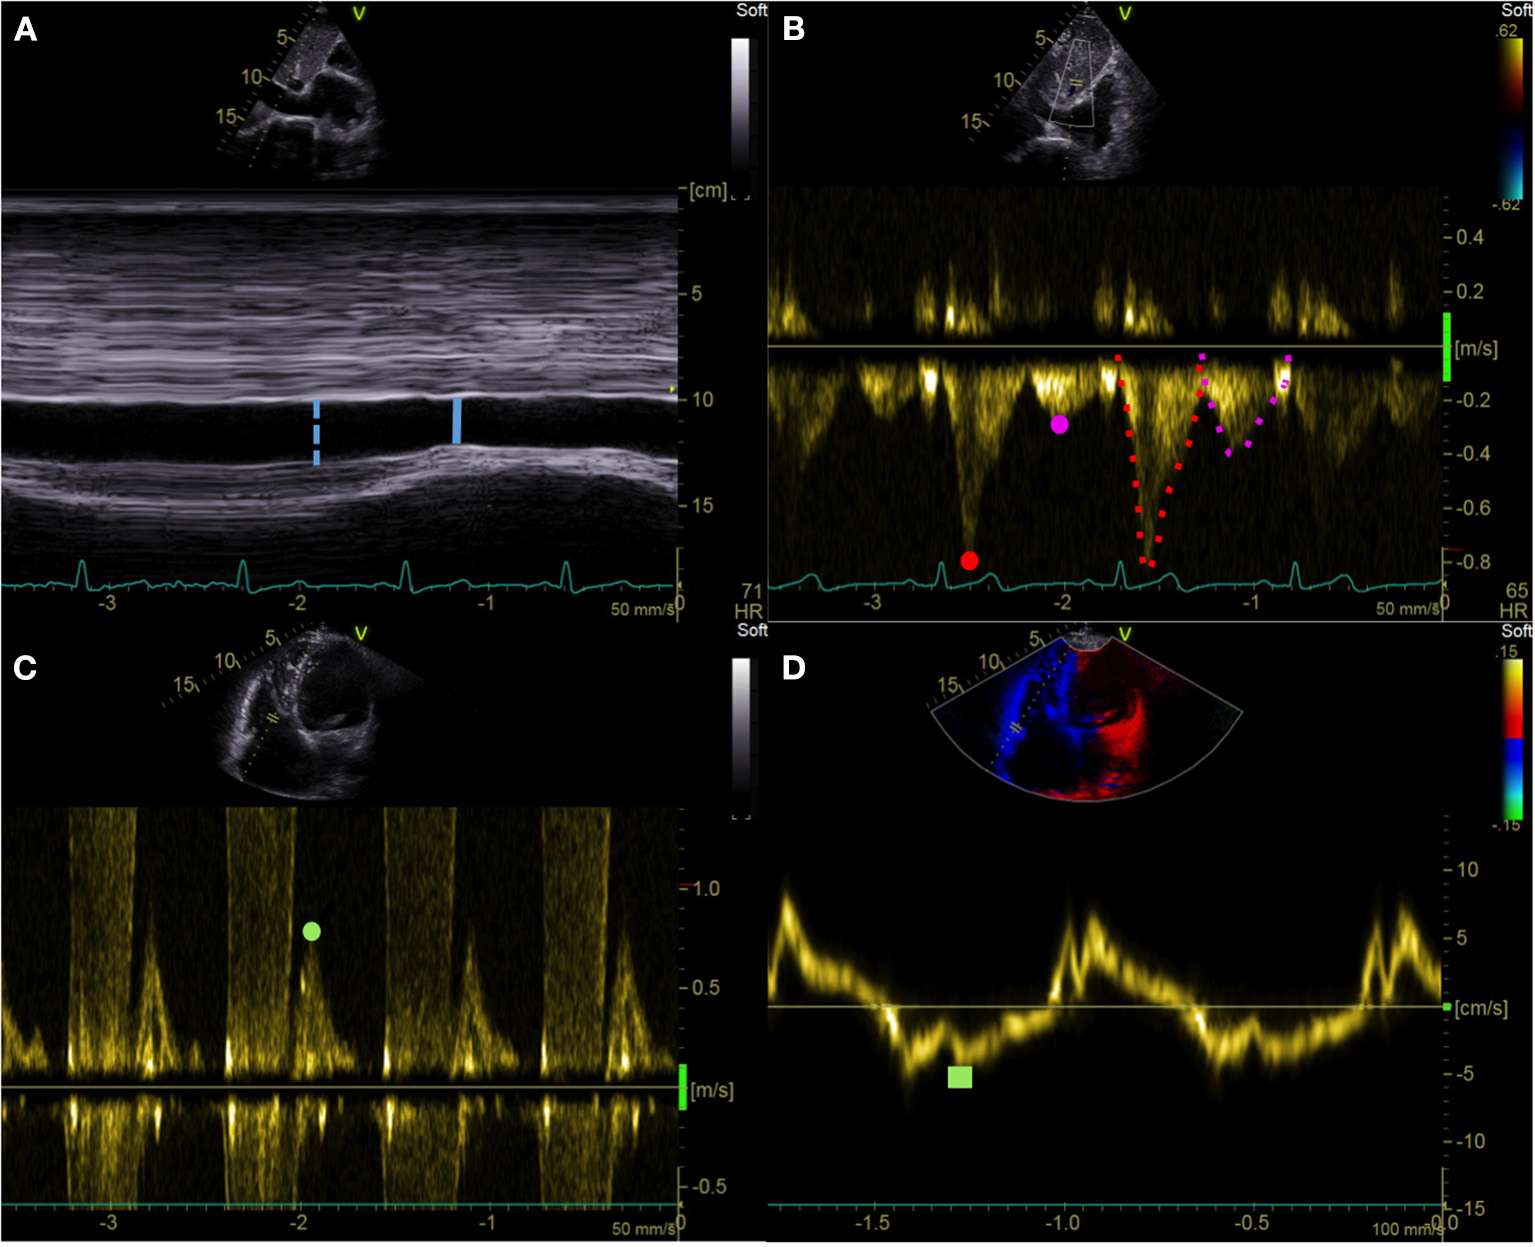

eRAPIVC, , and eRAPHV were given a value between 5 and 20 mmHg on a 5-mmHg scale as summarized in Table 1 and exemplified in Figure 1. eRAPmean was calculated as (eRAPIVC + + eRAPHV)/3 and thereby consisted of continuous values.

Figure 1

Echocardiographic right atrial pressure estimation. (A) IVC end-expiratory diameter (blue dotted line) and respiratory variation (solid line). (B) HV pulsed wave Doppler assessment: Vs (red dot), Vd (purple dot), VTIs (red dotted line), and VTId (purple dotted line). (C,D) Tricuspid E/e′ ratio: pulsed wave Doppler tricuspid inflow early E-wave peak velocity (green dot) and tricuspid lateral annulus tissue Doppler imaging e′ wave velocity (green square). IVC, inferior vena cava; HV, hepatic vein; Vs, hepatic vein peak systolic velocity; Vd, hepatic vein peak diastolic velocity; VTIs, velocity-time interval of the HV systolic wave; VTId, velocity-time interval of the HV diastolic wave.